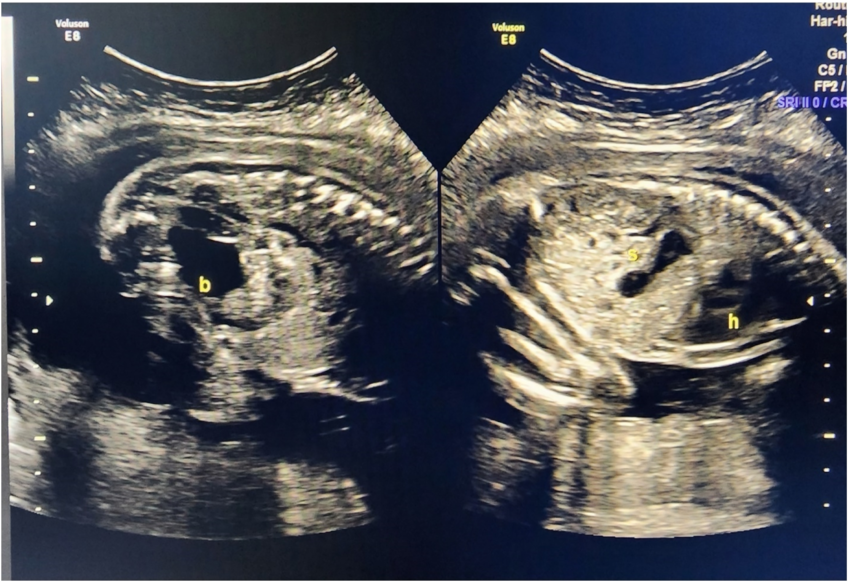

The Fetal Wellbeing Scan is performed to assess:

• The size and growth of the baby

• The amniotic fluid surrounding the baby

• Placental resistance to blood flow

• The baby’s overall state of health

This scan is usually done around 32 weeks of pregnancy and is recommended for all expecting mothers.

At Zenith Hospital, Nagpur, Dr. Manasi Thakur offers advanced Fetal Wellbeing Scans using the latest ultrasound technology. The results help guide mothers on the right precautions and care to ensure a healthy pregnancy and baby development.